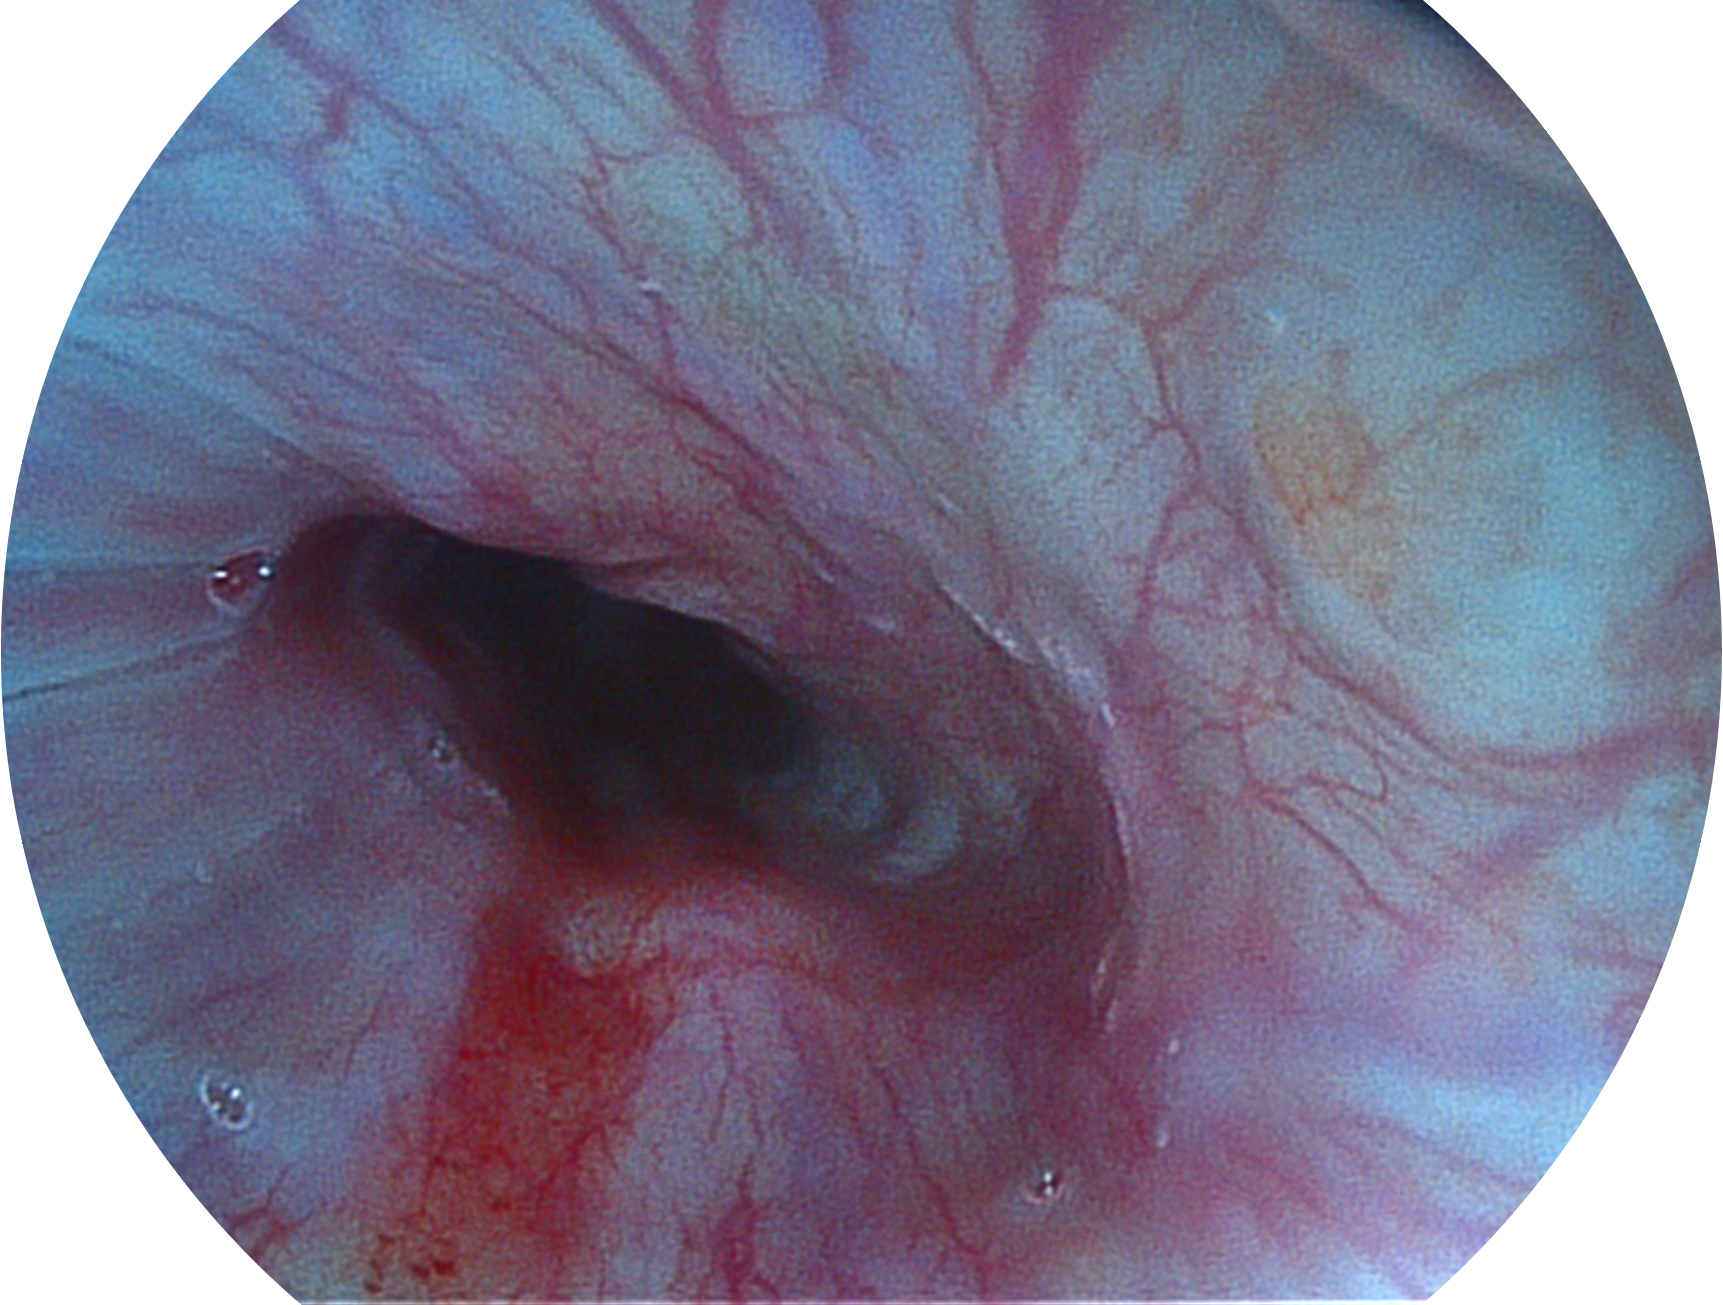

玖鼎集团新开发的内镜染色技术,主要是基于多波长LED 光源的开发,VLS-55Q 四波长LED 光源是由四个不同颜色的LED光按照相应照明模式所规定的特定发光比例进行合束后形成,合束后形成的照明光的光谱由红光、绿光、蓝光及蓝紫光这四个不同的波段范围构成。具有更高光谱自由度,通过光谱比例的控制,实现了聚谱成像技术,英文全称为“Spectral Focused Imaging, SFI”,缩写为“SFI”和光电复合染色成像技术,英文全称为“Versatile Intelligent Staining Technology, VIST”,缩写为“VIST”。